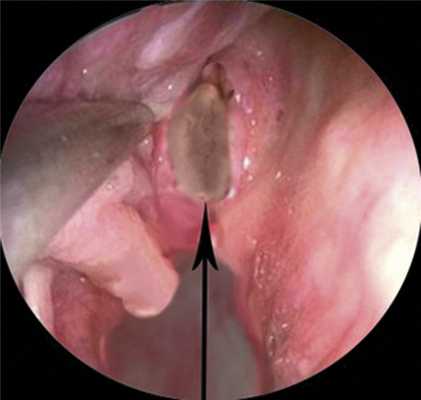

После удаления полипа пациенту было проведено эндоскопическое исследование полости носа, при котором определялось патологически расширенное соустье правой клиновидной пазухи. Слизистая оболочка на нижней стенке была полипозно изменена, визуализировался остаточный фрагмент ножки полипа, который вместе со слизистой оболочкой был удален щипцами Блексли (рис. 3). Рис. 3. Эндоскопический обзор патологически расширенного устья клиновидного пазухи, вызванного сфенохоанальным полипом.